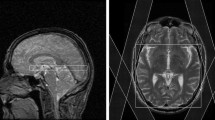

All subjects underwent a MR examination at 3T (Verio, Siemens, Erlangen, Germany) with a 12 channel phased array head coil [9, 10, 16]: For quantitative MR measurements the following scan sequences with a field of view of 256 × 208 mm2 and a 3 mm thickness in axial section were used: a T2-weighted turbo spin-echo sequence with 3 echoes (triple echo) (T2wTSE, TR/TE = 6640/8.7/70/131 ms, 150° flip angle), a T2*-weighted gradient-echo sequence with triple TE (T2*wGRE, TR/TE = 1410/6.42/18.42/30.42 ms, 20°flip angle), and a T1 weighted three-dimensional (3D) GRE sequence with two flip angles (T1wGRE, TR/TE = 15/1.64 ms, flip angles 5° and 25°). For wbMRSI a T1-weighted 3D magnetization prepared rapid gradient echo (MPRAGE) acquisition at 1‑mm isotropic resolution for anatomic reference and a volumetric spin-echo planar spectroscopic imaging (EPSI) sequence (TR/TE = 1550/17.6 ms, 50 × 50 voxels in-plane and 18 slices, over a field of view of 280 × 280 × 180 mm3) were used, where the EPSI acquisition included a second dataset obtained without water suppression that was used for several processing functions and for internal signal reference for the normalization of metabolite concentrations as described previously [19]. To ensure identifying the same anatomic structures, all scans were obtained with the same angulation. The T2 and T1 weighted images were inspected by two experienced neuroradiologists to exclude subjects with morphological abnormalities. Brain maps of the tissue parameters were derived from scanned MRI data. For quantifying transverse relaxation process of brain tissue, the parameters T2 (irreversible relaxation time), describing proton spin-spin interactions, and T2’ (reversible relaxation time), characterizing local magnetic field inhomogeneity, were considered. The T2*-maps (effective relaxation time) related to both mechanisms together were used to obtain T2’ according to the relationship 1/T2’ = 1/T2* − 1/T2. Brain T2-maps were obtained on the MR system with an extended image reconstruction using monoexponential fitting to the signal intensity decay curves of the data acquired with triple echo T2wTSE sequence. The T2*-maps were reconstructed in a similar way from the data acquired with triple echo T2*wGRE sequence, and the T1-maps from the data acquired with T1wGREsequence. Subsequently the T2’-maps were derived according to the relationship mentioned above.

a Locations of each selected region of interest in the right brain hemisphere displayed as white filled circles on T2-weighted images of a 21-year-old healthy volunteer. The numbering represents the ROIs in the hand motor cortical area (1), postcentral gyrus (2), cingulate gyrus (3), splenium of the corpus callosum (4), thalamus (5), occipital area (6), temporal lobe lateral (7), temporal lobe medial (8), insular gyrus (9), hippocampus (10), cerebellum anterior lobe (11) and cerebellum posterior lobe (12). b Example metabolite maps of NAA, Cho, tCr, Glx, mI and spectral linewidth at the section level of the posterior cingulate gyrus with an example MR spectrum derived from wbMRSI. c Example tissue parameter maps of T2’, T1 and T2 at the section level of the posterior cingulate gyrus

Figure 1 shows the locations of selected regions of interest (ROI) in the right brain hemisphere, displayed as white filled circles or oval on the T2-weighted images of a 21-year-old female volunteer (Fig. 1a), the example tissue parameter maps and the metabolite maps at the section level of selected posterior cingulate gyrus ROI (Fig. 1b, c).